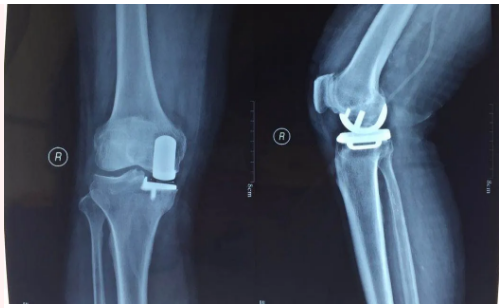

單踝置換

膝關節(jié)置換

嚴重膝關節(jié)疾病導致全膝破壞的終極治療是膝關節(jié)置換,骨二科采用內軸膝系統,能更好的模擬膝關節(jié)的正?;顒?,完美恢復膝關節(jié)的功能,達到Forget knee的效果。